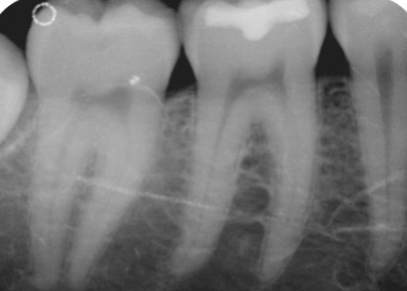

Cone Cut

What it looks like:

A clear white semicircle on the radiograph.

Cause:

The X-ray beam was not centered on the receptor.

Fix:

Center the PID properly.